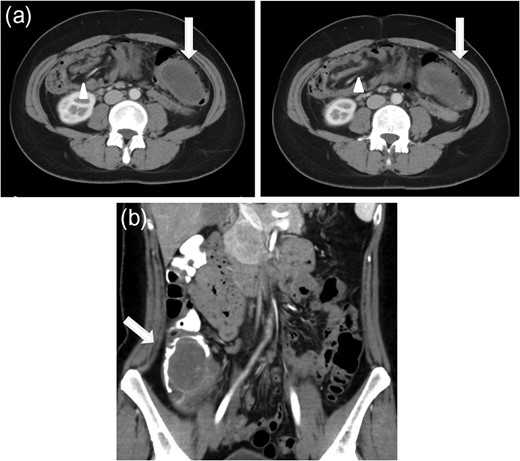

(a) Axial CT scan of the abdomen showing a mass (arrow) filling the transverse colon with accompanying mesenteric fat and vessels (arrowhead) within the lumen. (b) Coronal CT scan after reduction by colonoscopy. A low-density mass (arrow) is pushed back into the caecum.